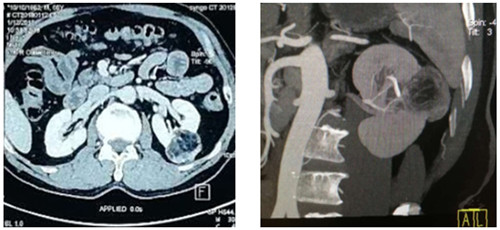

如圖一圖二為腫瘤位置及大小,圖三即為手術(shù)操作通道(5mm、10mm、12mm),術(shù)中游離出腎動(dòng)脈后,用圖四的血管夾臨時(shí)阻斷腎臟血液供應(yīng),剜除腫瘤后,在腔鏡下縫合腎臟,確定縫合嚴(yán)密,再恢復(fù)腎臟血供!要求阻斷時(shí)間不能超過(guò)30分鐘,此例患者阻斷17分鐘!此類手術(shù)技術(shù)難度大,腹腔鏡下縫合要求高,并對(duì)血供阻斷有時(shí)間要求!